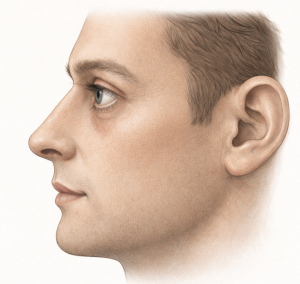

- Tear trough hollowing

- Lower eyelid retraction or increased scleral show

- Higher risk of lower eyelid malposition after blepharoplasty

- A fatigued or skeletonized facial appearance